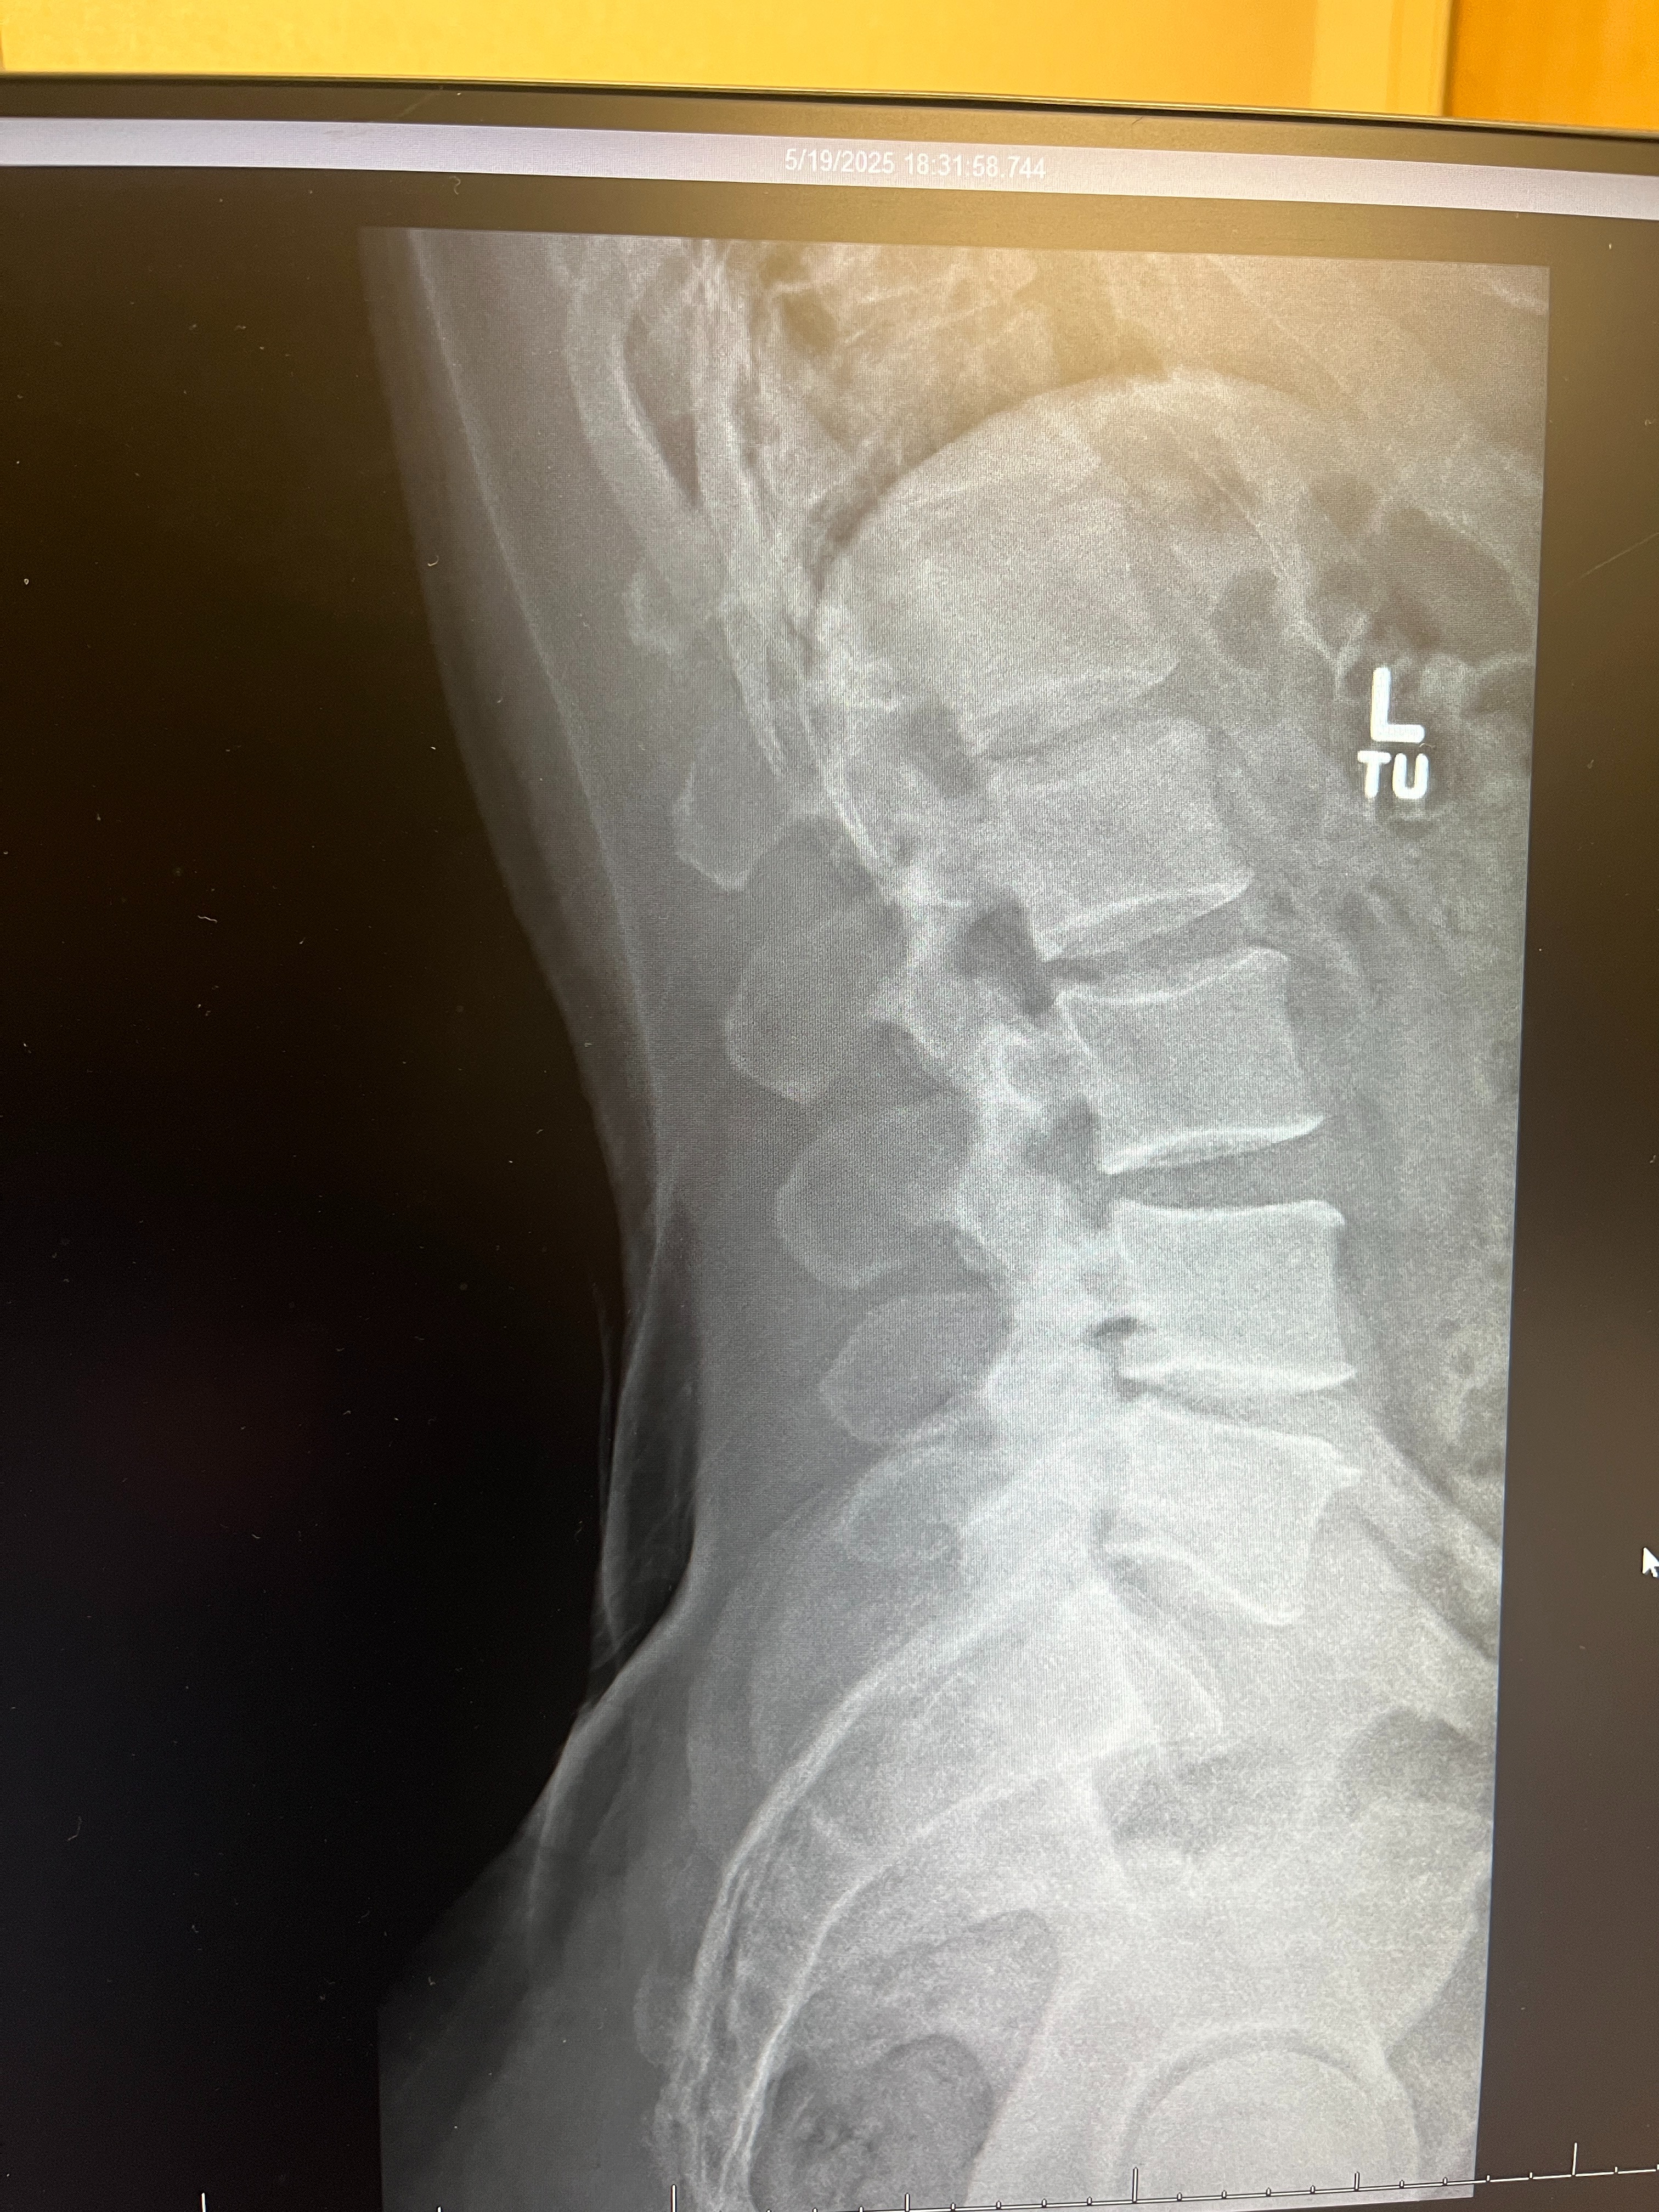

Hello Everyone, I'm in need of a spinal stem cell treatment to stop this injury from getting worse. I had a major spinal injury at the age of 26, and doctors have always told me that eventually I'd need back surgery, but, I did intense rehab and made healthy lifestyle choices over the years and stretched that time I feel as far as I could, however, I still don't want to go under the knife and have surgery. My close friends that have had spinal surgery all wish they didn't do it but at the time there wasn't an alternative, now there is one. I'm 40 years old now and I know a stem cell procedure is my best option to have my body heal itself. I have Spinal Stenosis, Degenerative Disc Disease and Disc Herniations. I've done rehabilitation. I eat right and take care of my body, but, nerve pain affects even the strong and healthy athletes, not just people who aren't athletic and not in shape. The pain from this is unbearable, and I'm currently not working because of this injury. I don't earn enough in order to attain this goal for this procedure, however, I've always been a hard worker and have career dreams and goals like anyone else. I always do my very best to achieve those dreams and goals, but as of right now my only focus is to get better. I need your help in order to do that. If you can, please donate and share this campaign with others, and if you cannot donate, I truly understand that and thank you so very much with all my heart and soul for your time. I do humbly ask however that you please pray for me regardless. I know that's more powerful than anything else. I do my best to build my relationship with GOD, and I'm very aware that my own sins have led me to where I currently am, and I have to truly repent and seek forgiveness for my choices and actions out of harmony with God's Love & Truth and loving Laws of the Universe. I continue to pray to receive God's Love and Truth into my soul to build my relationship with God and I pray you all one day desire the same. Thank you again for your time and your help. God Bless you all.